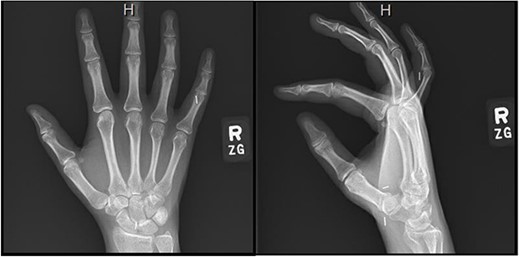

Four months postoperatively, the patient presented with complaints of pain at her small finger distal interphalangeal joint, and verbalized feeling small staples at the symptomatic site. Radiographic imaging demonstrated that the three previously placed hemoclips had migrated along the flexor tendon tract to the volar aspect of her right small finger proximal interphalangeal joint (Fig. 3). Surgical excision of the clips involved utilizing a Bruner-style incision volarly followed by a small window into the tendon sheath. One hemoclip was identified at the level of the proximal interphalangeal joint sandwiched between the flexor digitorum profundus and the superficialis tendons. Two more clips were identified proximally.

Right hand imaging 4-months status post revision CTR demonstrating symptomatic triple hemoclip migration into the volar aspect of the small digit.